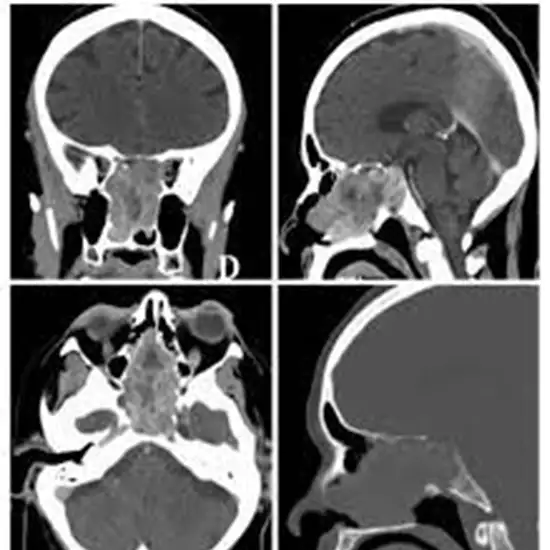

A CECT Pituitary Sella or Contrast-Enhanced Computed Tomography of the Pituitary Sella is an imaging technique that creates multiple cross-sectional images of the pituitary Sella using highly focused radiation (X-ray beams) and contrast dye material (small, bony nook at the base of the skull). The images obtained using this method aid physicians in determining and assessing abnormalities in the pituitary Sella, which protects the brain.

A CECT Pituitary Sella is a painless, non-invasive procedure. However, the use of contrast material during the procedure can occasionally result in side effects. Abnormalities in the test scan report may help identify the presence of empty Sella syndrome (a condition that causes pituitary gland shrinkage), tumour, or any other conditions affecting the pituitary gland or Sella turcica.